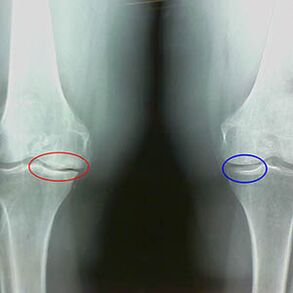

The arthrosis degree is determined by X -RayExchange of participation in the pathological process of bone structures.Their change shows that the muscle system has had an imbalance for 5 to 10 years.Usually peopleYou experience painful pain for several years.

The second stage of osteoarthritis is viewed as simple.The X -ray image shows significant bone spores, but the cartilage is not affected.The amount of synovial fluid is reduced, but after long walking and running pain symptoms, stiffness in the joint and pain when bending and in the position on the knees occur.

Early X beam features of the second stage of the knee arthrosis:

- The pointed edges of the internal tubercles on the Tibia, to which the cross -defined band is attached;

- Narrowing of the common gap on the medial side;

- The pointed edges of the bone condyl on the medial sides, less often in the side - depending on the development of the valgus or the deformation of the variant connection.

For the second stage in LarsenThe narrowing of the common gap by more than 50% is characteristicHowever, this can only be checked in dynamics or in comparison with an uninterrupted of joints.

The X -ray image shows the presence of osteophytes, a change in the space between the Femur and Tibia bones, which indicates the cartilage loss in the knee.Sometimes the x rays of the knee joints show significant signs of cartilage wear, but patients have no significant pain.On the contrary, the arthrosis of the first stage can disturb the function of the kneeThe cause of the pain is hypotonic muscles.